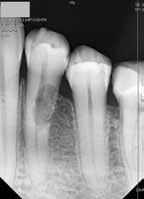

kép]. Az üregben nagy mennyiségű gyulladásos szövetet találtunk, mely eltávolítása után láthatóvá vált a kavitás kiterjedése [13. kép]. A kisőrlő fogakra jellemző tengelyirányú, valamint oldalirányú terhelés kombinációja, valamint a je-

lentős foganyagveszteség miatt szerettük volna a lehető legjobban megerősíteni a fogat. A terület kofferdám gumilepedővel történő abszolút izolálása után a gyökércsatornát egy guttapercha segítségével kiblokkoltuk, ezzel megelőzve

a csatorna obliterálódását [14. kép]. Ezután megfelelő adhezív előkezelést követően kompozit tömőanyaggal restauráltuk az elváltozást (Essentia Universal, GC Europe) [15. kép]. Finírozást és alapos polírozást követően zártuk lebenyünket, majd újabb kofferdám izolálásban elvégeztük a fog gyökérkezelését [16. és 17. kép]. A kezelést követően páciensünk teljesen panaszmentes volt. Két hónapos kontrollon a fog teljesen ép, az íny tökéletes kitapadását tapasztaltuk [18. és 19. kép] Szondázási mélység a bukkális oldalon mindenhol 2 mm alatt volt.